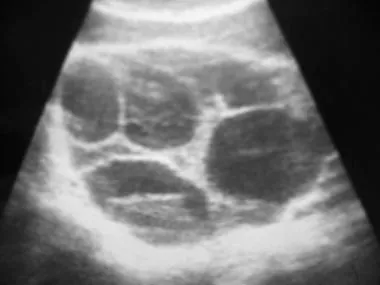

Theca lutein cysts are bilateral cysts caused by excess hCG stimulation of the theca interna. Often multiple cysts form multiple follicles.

- Associations Anything that increases hCG

- Chlomiphene for IVF

- Gestational trophoblastic disease

- Multiple gestation

- Diabetes mellitus